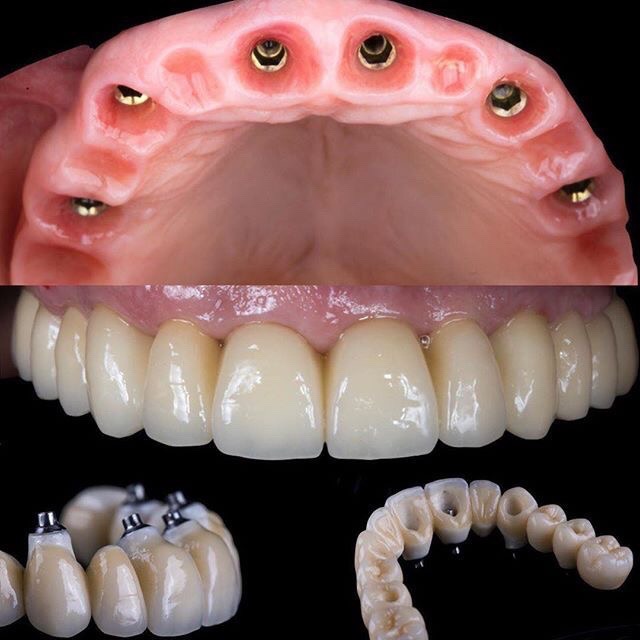

二、手術階段(1次)

• 植入人工牙根:將植體放入缺牙位置的牙骨中。

• 補骨或牙齦處理(如需要):若骨量不足,醫師會同步補骨。

• 臨時假牙:部分患者可裝戴臨時牙冠,美觀不受影響。

四、裝戴假牙(1-2次)

• 試戴與調整:確保咬合舒適、外觀自然。

• 完成固定:正式假牙裝戴完成,植牙療程告一段落。